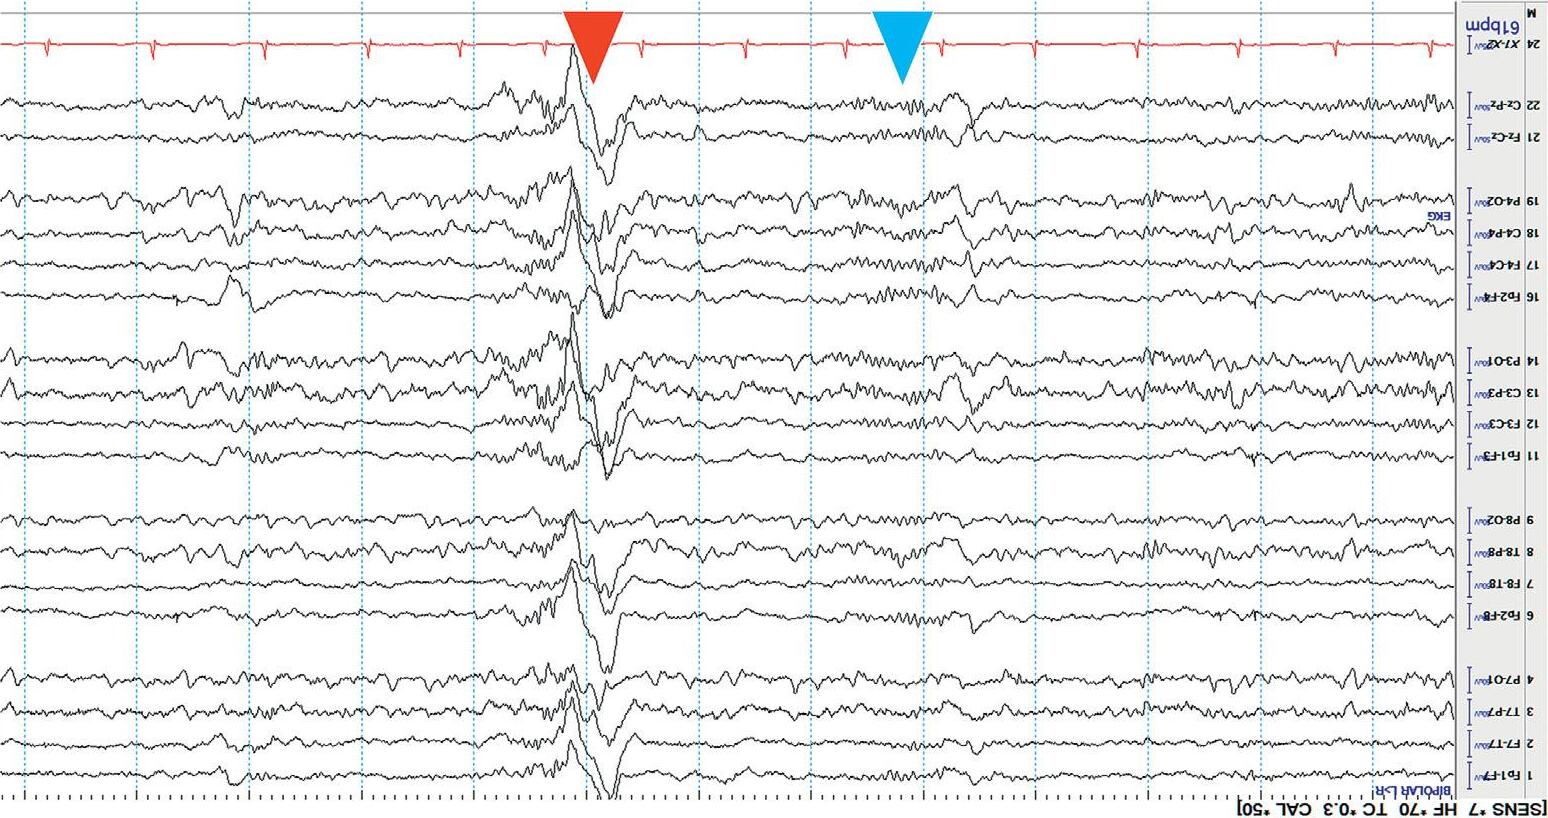

Channels(electrodepairs)aredisplayedontheEEGscreenusingspecific arrangements.Thesespecificarrangementsarecalled montages. Therearemanydifferenttypesofmontages,detaileddescriptionsofwhich arebeyondthescopeofthisbook.However,acutecareprovidersshouldbe familiarwithusingalongitudinalbipolar(doublebanana)montage,asthisisa commondefaultmontageandeasytouseatthebedside.AllEEGexamplesin thisbookusethismontage.

Eachchannelofalongitudinalbipolarmontageshowsthepotentialdifferencebetweentwoadjacentelectrodesonthescalp,andisconnectedtoother channelsinlongitudinal(fronttoback)chainsasshownbelow[3].

Figure1.3(a) showsanexampleofthelongitudinalbipolarmontage,while Figure1.3(b) showsaschematicrepresentationofitselectrodechains.

Figure1.3(a) EEGinlongitudinalbipolarmontage.

Atypicalbedsidedisplayusingalongitudinalbipolarmontageisshownin Figure1.3(a). Variationstothisformatexist.Commonly,theleftandtheright temporalchainsarestackedtogetherfollowedbytheleftandrightparasagittal chains.Thismakesiteasytocomparethetemporalandparasagittalregionsof bothhemispheresforasymmetry.Readersshouldknowthatthetemporal regionsarealsothemostepileptogenicsofocusingonthesechannelsyields results!Thetopbarofarecordingshowsthesensitivity,filtersettings,and timebase.